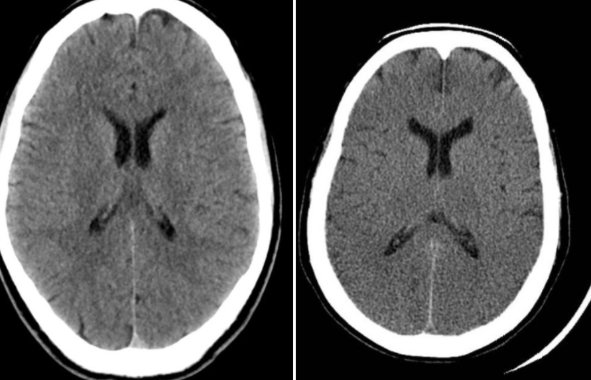

What is hydrocephalus, and what does it look like on CT head?

A

Hydrocephalus: Abnormal accumulation of CSF in brain ventricles and spinal cord

CT finding: Ventricles look swollen with loss of sharp points, with dark colour (hypodense due to fluid accumulation)